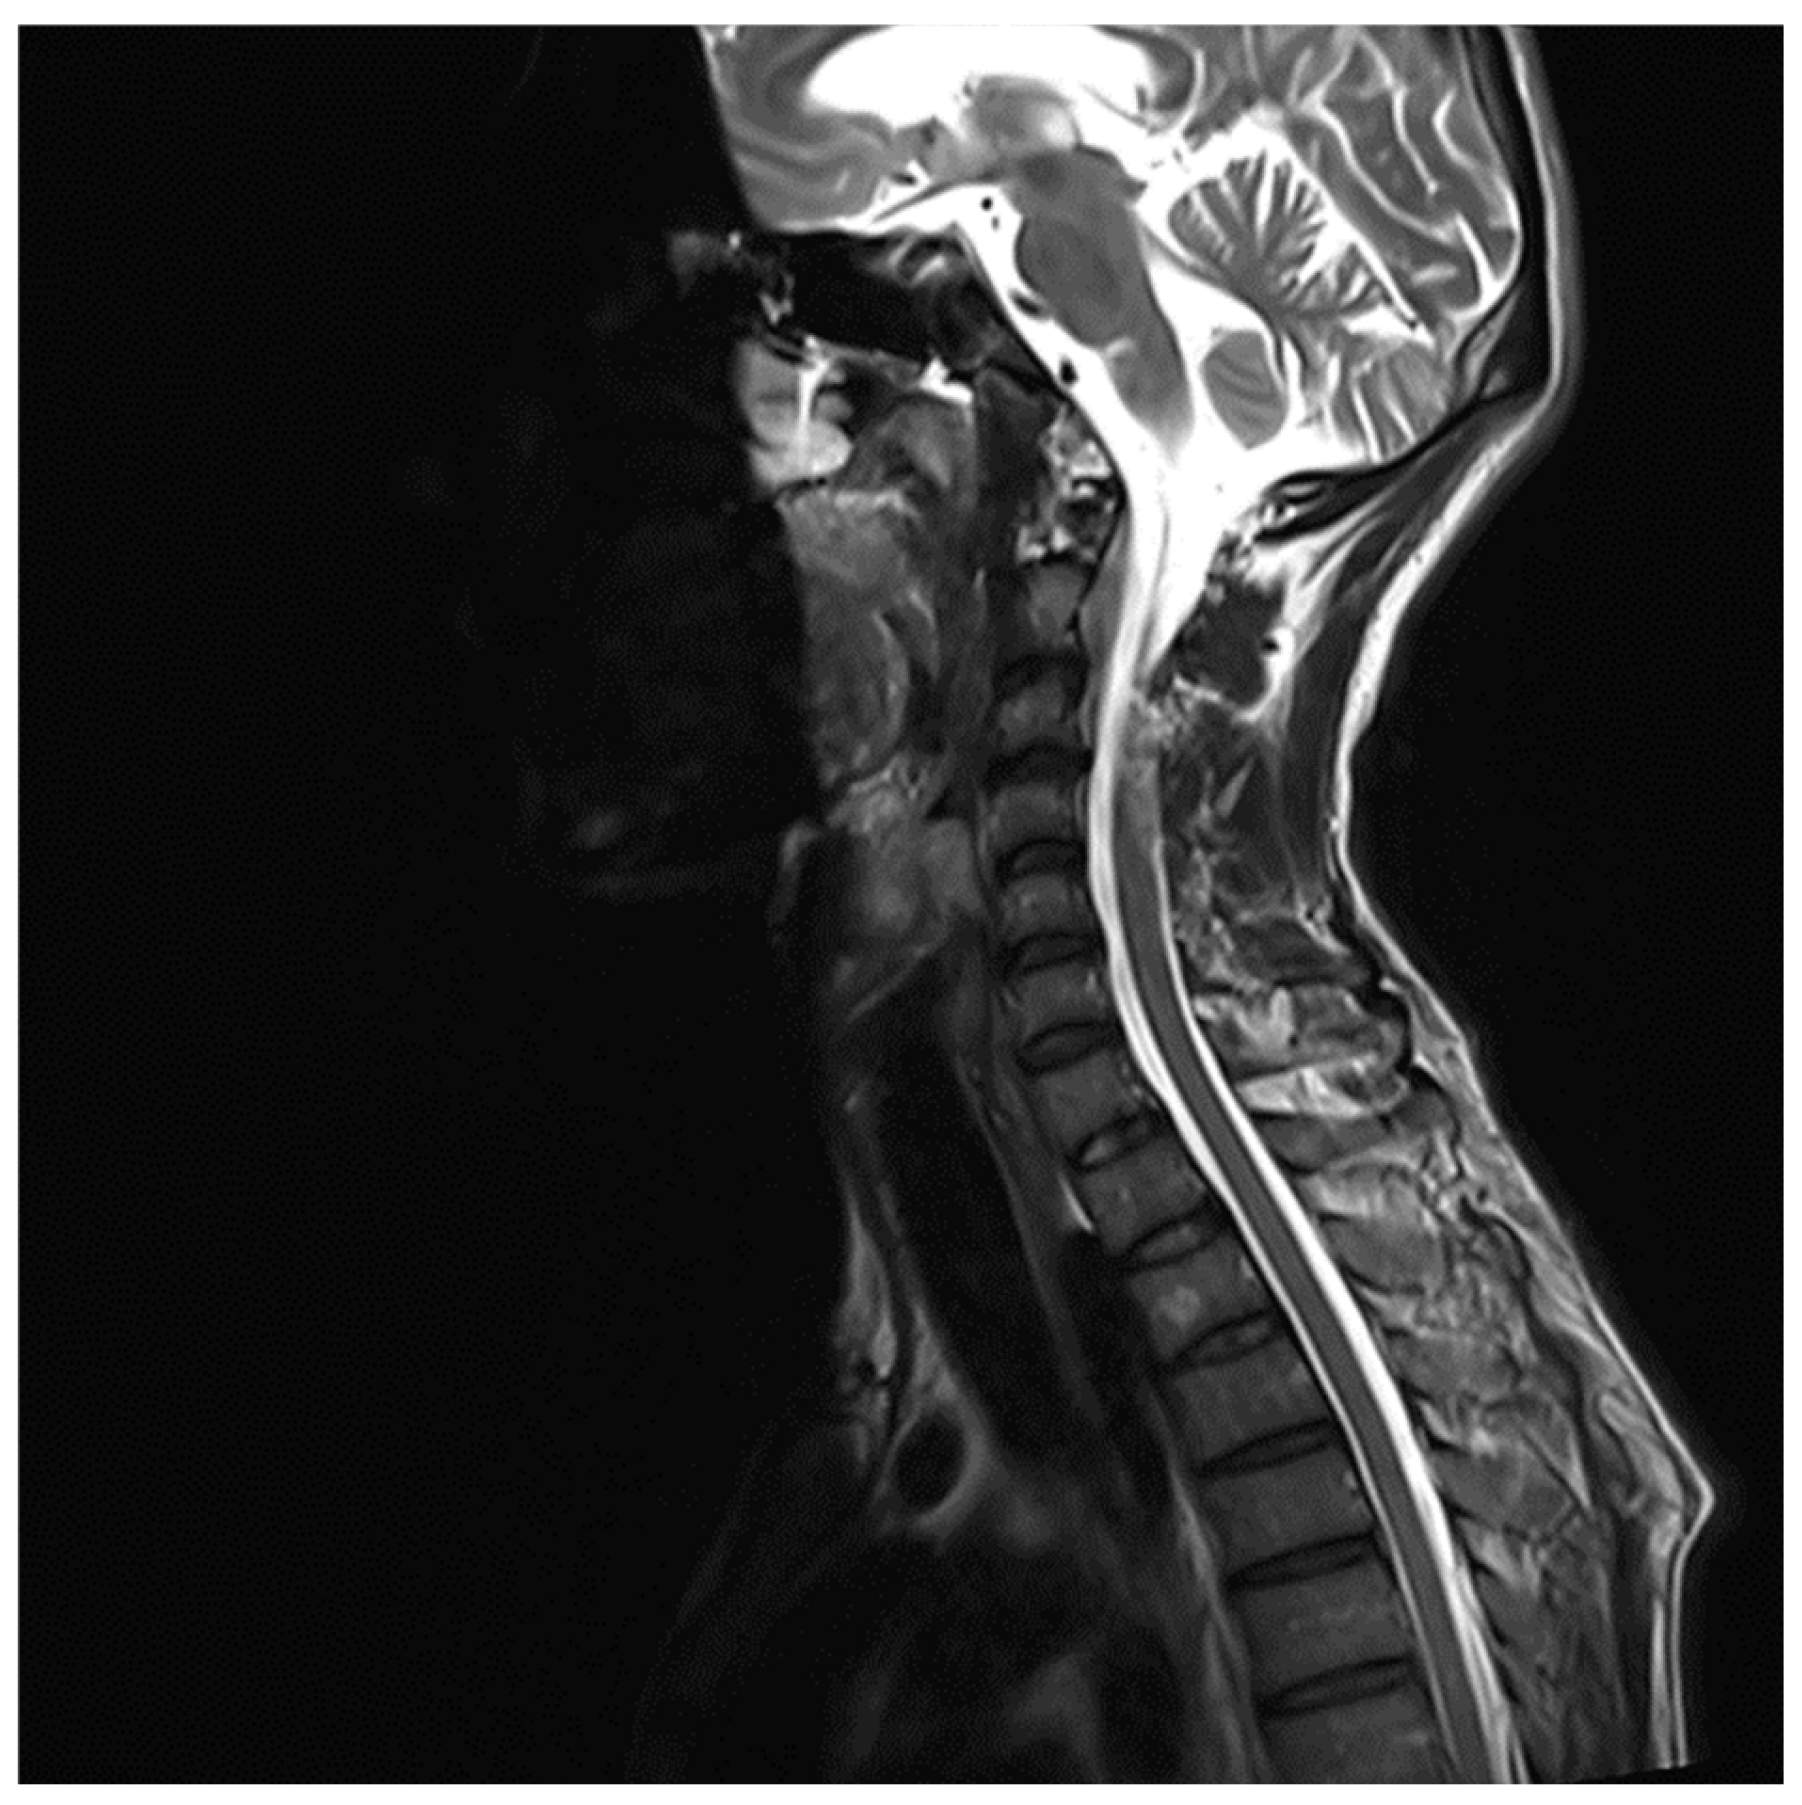

MRI whole spine screening showed early disc desiccation at upper cervical vertebral levels. Haemangioma was noted in the body of the D2 vertebra. C3-C4 level showed disc osteophytes complex causing indentation over anterior thecal sac without causing significant nerve root compression. Repeated MRI Spine showed an abutment over the right exiting nerve root at the above-mentioned level. L5-S1 level showed diffuse disc bulge causing bilateral lateral recess stenosis, neural foraminal narrowing and indentation over the anterior thecal sac with resultant abutment over bilateral exiting nerve roots. Above-stated findings give evidence of demyelinating Balo’s Concentric Sclerosis.

Figure 5. MRI Spine C3-C4 level.